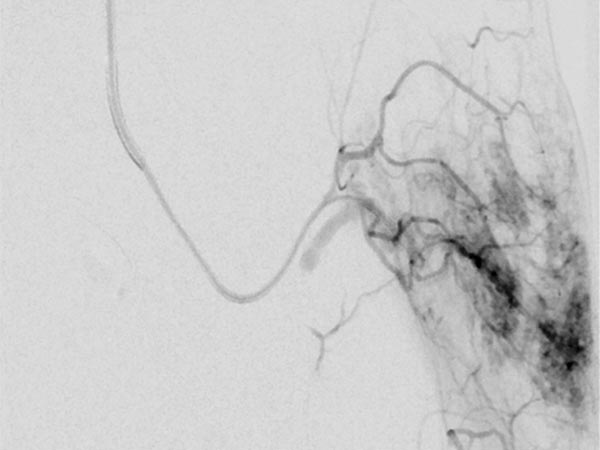

On B-scan ultrasonography (top image), the tumor is relatively homogeneous, hypoechoic, and clearly solid, not compressible. Color-coded duplex ultrasonography (bottom image) shows intense perfusion via multiple arterial vessels. This is suggestive of a congenital vascular tumor and, in this case when combined with the bluish appearance, the special case of a congenital hemangioma.

Control sonography (color-coded) at 4 months of age shows no change in echogenicity, especially no signs of involution. Continued strong perfusion and no increase in echogenicity, as would be the case with a rapidly involuting congenital hemangioma (RICH).